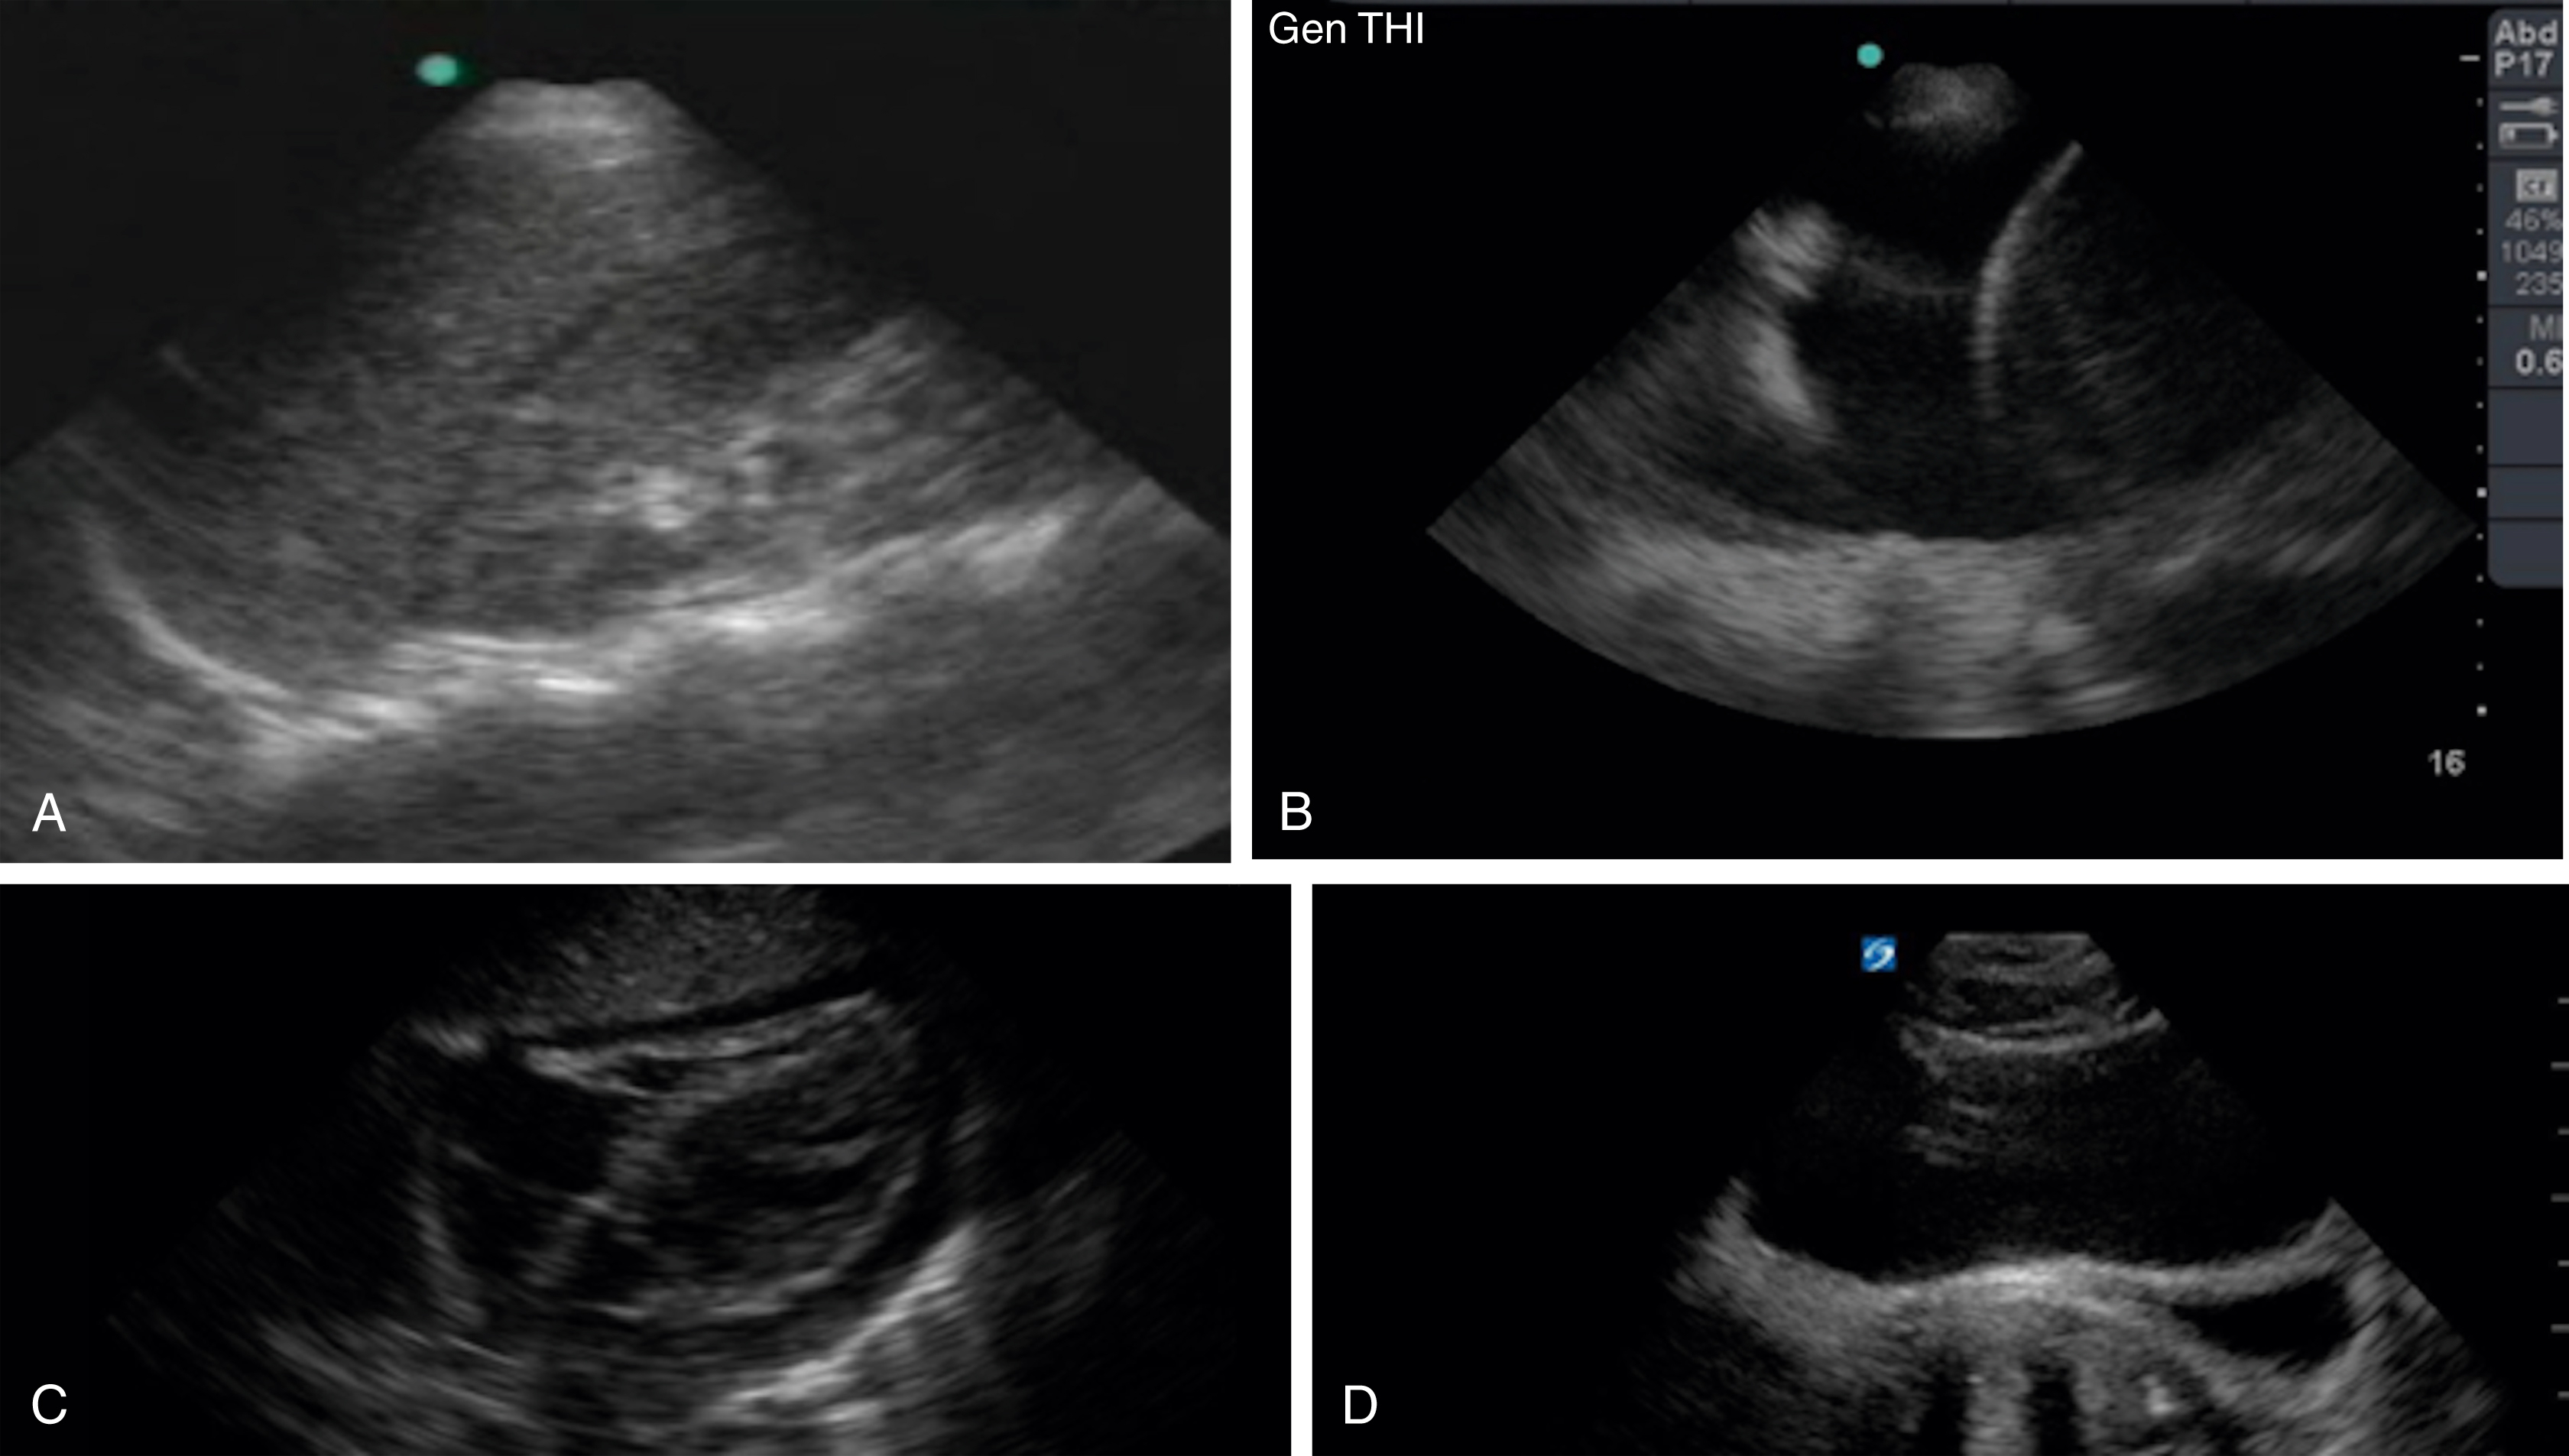

The visualization of lung sliding excludes the presence of a pneumothorax at that location on the patient’s chest wall. Although M-mode and color Doppler techniques have been described as adjuncts to the evaluation of patients with suspected pneumothorax, neither is a necessary component of the examination. Absent lung sliding can result from a variety of causes in addition to pneumothorax, including pleural adhesions or consolidations, blebs, pleurodesis, partial or complete pneumonectomy, and contralateral mainstem bronchus intubation ( Fig. e3.15 ). A lung point sign is identified at the border of the pneumothorax, where the image shows absent lung sliding until the lung moves into the interspace with respiration ( Video e3.12 ).

Fig. e3.15

M mode images of the lung. (A) Normal lung with “seashore” sign. (B) Pneumothorax with “stratosphere” or “barcode” sign.